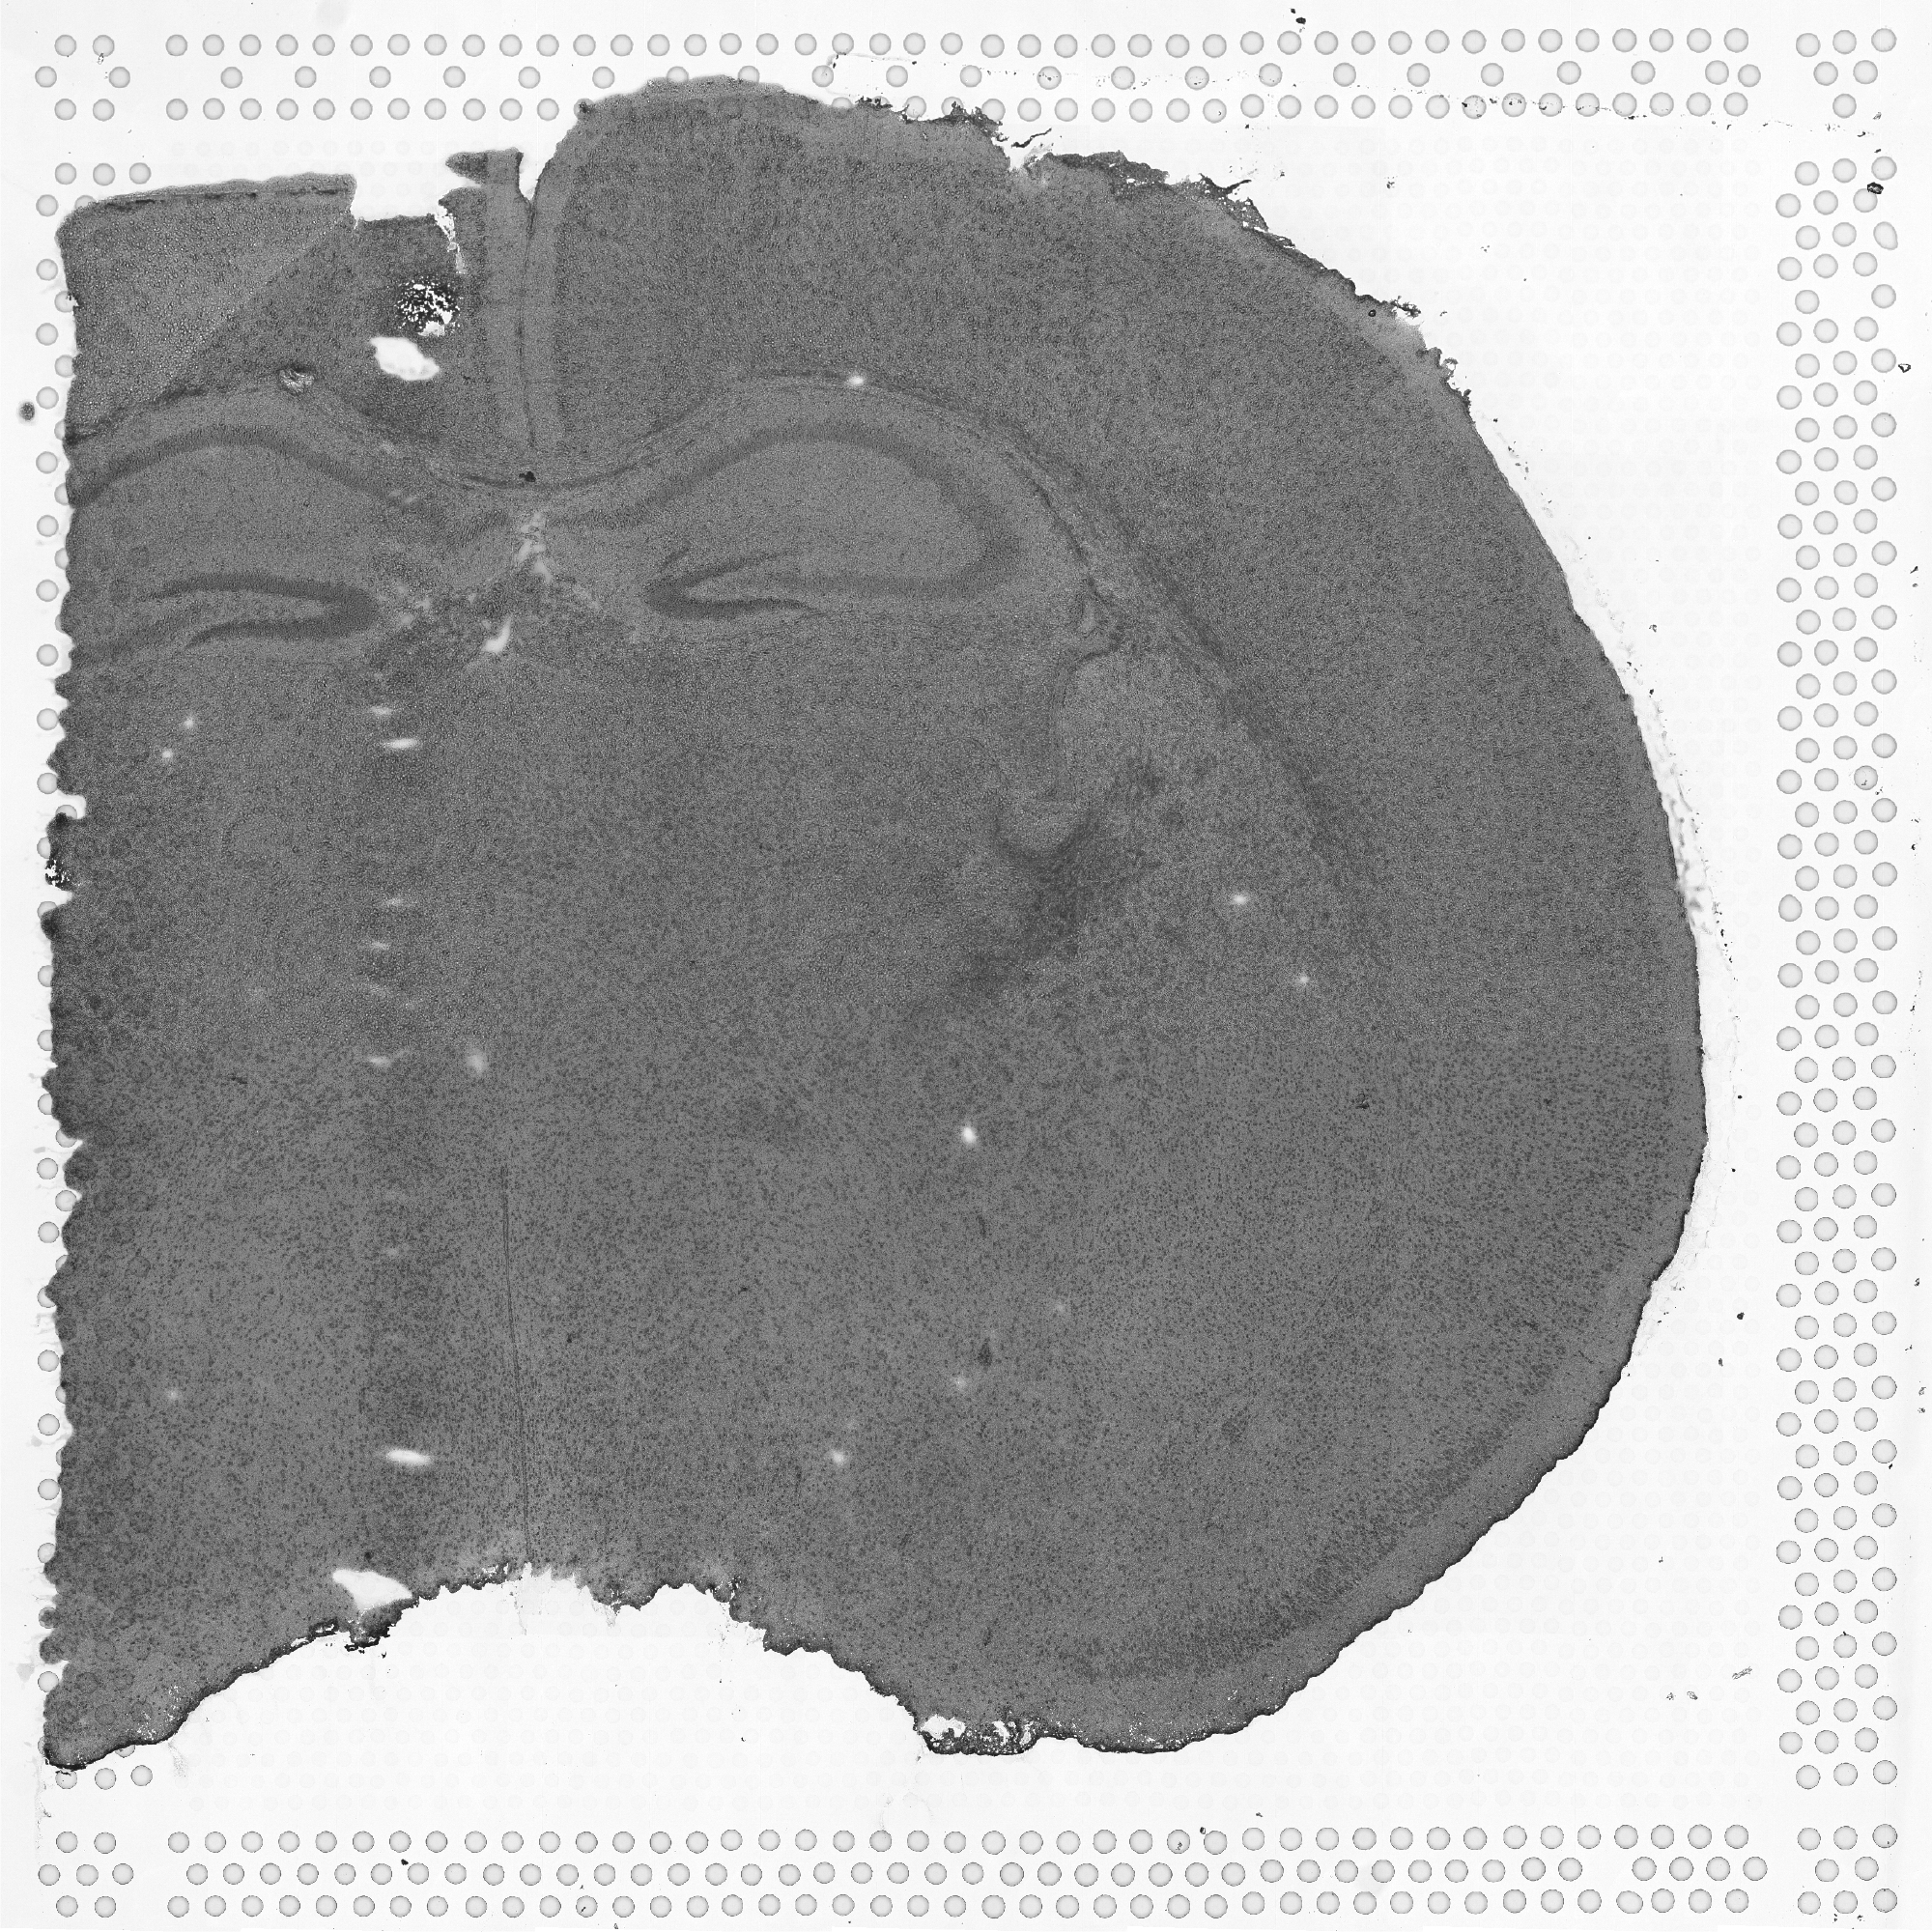

tissue_hires_image.png